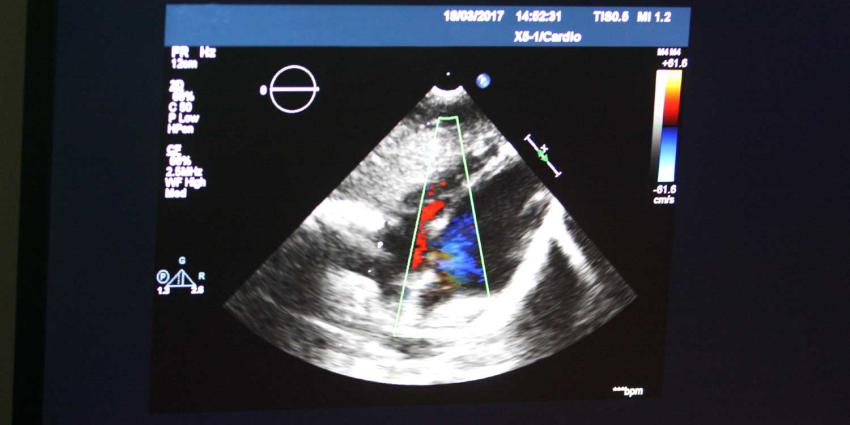

echo-hart-cardio

Foto: Archief EHF/ foto ter illustratie